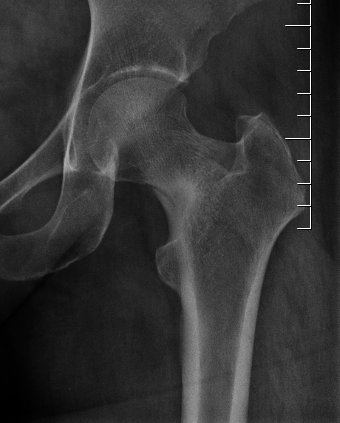

Xray

Can be normal

Sclerosis / fracture line

Increased sclerosis at inferior neck Xray demonstrating incomplete fracture of the superior neck